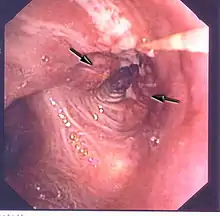

Le cancer du poumon peut être vu sur les radiographies thoraciques et le scanner. Le diagnostic est confirmé par une biopsie. Ceci se fait généralement par bronchoscopie, ou par biopsie guidée par scanner. Le traitement et le pronostic dépendent du type histologique du cancer, de son stade (degré de dissémination), et de l'état général de santé du patient.

La radiographie thoracique est la première mesure à prendre si un patient se plaint de symptômes pouvant suggérer un cancer du poumon. Ceci peut révéler une masse évidente, un élargissement du médiastin (qui suggère une extension aux ganglions lymphatiques qui s'y trouvent), une atélectasie (affaissement), une inflammation (pneumonie) ou un épanchement pleural. En l'absence de signes radiographiques, mais si les soupçons sont élevés (par exemple, un gros fumeur avec hémoptysie), une bronchoscopie ou un scanner peuvent donner l'information nécessaire. La bronchoscopie ou la biopsie guidée par scanner sont souvent utilisées pour identifier le type de tumeur[3].